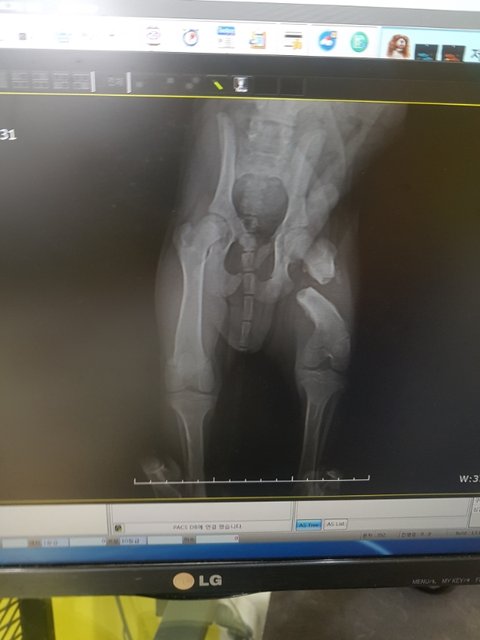

엑스레이상 뒷다리가 똑 부러져있습니다

사진을 보는것만으로도 아이의 고통이 전해져 명치끝이 아파옵니다